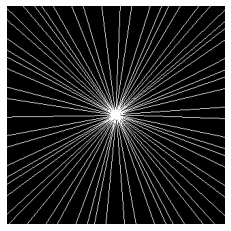

In spite of its extensive adaptation in almost every medical diagnostic and examinatorial application, Magnetic Resonance Imaging (MRI) is still a slow imaging modality which limits its use for dynamic imaging. In recent years, Parallel Imaging (PI) and Compressed Sensing (CS) have been utilised to accelerate the MRI acquisition. In clinical settings, subsampling the k-space measurements during scanning time using Cartesian trajectories, such as rectilinear sampling, is currently the most conventional CS approach applied which, however, is prone to producing aliased reconstructions. With the advent of the involvement of Deep Learning (DL) in accelerating the MRI, reconstructing faithful images from subsampled data became increasingly promising. Retrospectively applying a subsampling mask onto the k-space data is a way of simulating the accelerated acquisition of k-space data in real clinical setting. In this paper we compare and provide a review for the effect of applying either rectilinear or radial retrospective subsampling on the quality of the reconstructions outputted by trained deep neural networks. With the same choice of hyper-parameters, we train and evaluate two distinct Recurrent Inference Machines (RIMs), one for each type of subsampling. The qualitative and quantitative results of our experiments indicate that the model trained on data with radial subsampling attains higher performance and learns to estimate reconstructions with higher fidelity paving the way for other DL approaches to involve radial subsampling.